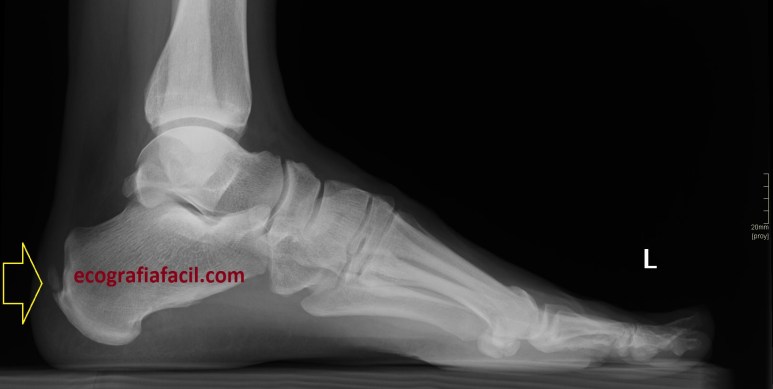

Corrobora si el paciente tiene estudios radiológicos simples que estén en concordancia con la imagen 10, por ejemplo, la imagen 12.

La flecha amarilla indica la que en la parte posterior del calcáneo existe un calcio tosco en esta rx lateral del pie en carga, pero es en la inserción, cuidado con esto, cuando se produce el Haglund, no es en la inserción, es antes, y se debe a la exostosis mencionada con anterioridad, mira, compara imagen 12 e imagen 13. La flecha roja es indicativa de Síndrome de Haglund.